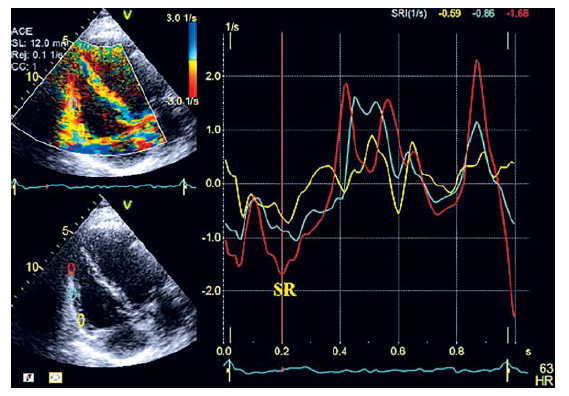

С помощью тканевого допплера можно измерить локальную систолическую скорость движения миокарда (S’), деформацию (S) и скорость деформации (SR) в сегментах свободной стенки ПЖ (рис. 5–7).

Рис. 7. Измерение SR в базальном, срединном и верхушечном сегментах свободной стенки ПЖ